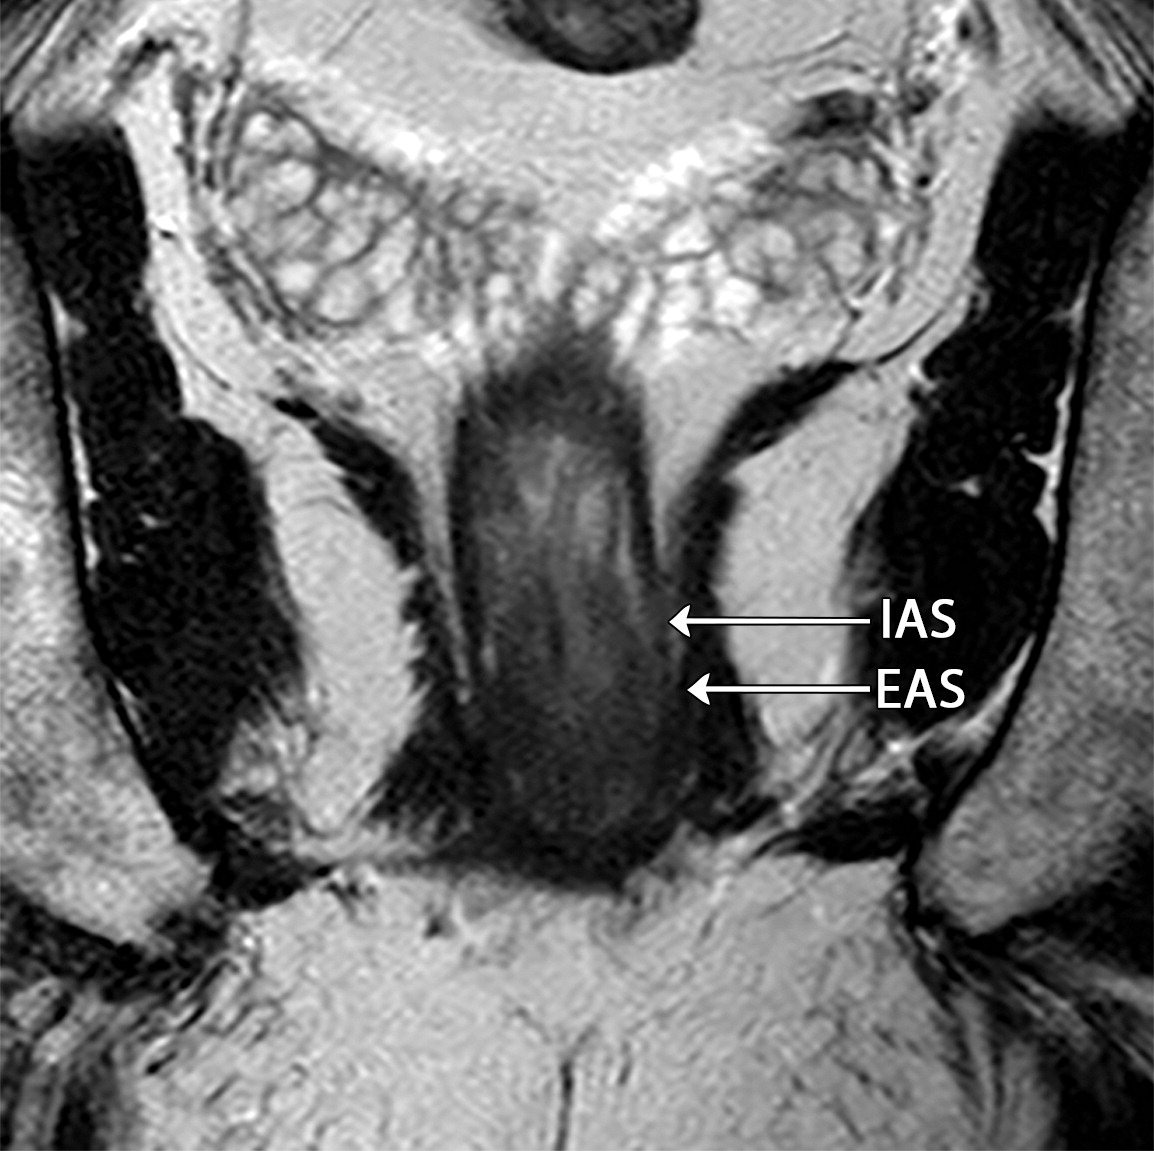

50岁以上男性骨盆和盆底的MRI解剖。

提肛肌(LA),由耻骨直肠肌(PR)、耻骨尾骨肌(PC)和髂尾骨肌(IC)组成;尾骨肌(C),前列腺(P),闭孔内肌(OI),会阴浅横肌(STP),球海绵体肌 (B), 坐骨海绵体肌(ISC),肛门外括约肌(EAS),肛门内括约肌(IAS),直肠(R),尿道括约肌(SU),也称为尿道外括约肌(U),它包围着整个膜性尿道。6774449af17bb1b8df6e83ab4e9fa158.jpeg